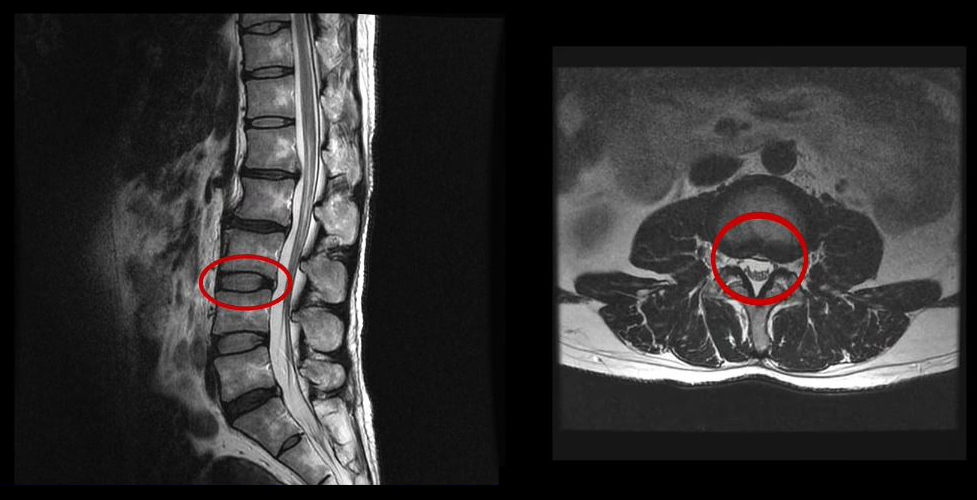

그런데 이 환자분의 MRI를 보면 여러 마디에 퇴행성디스크가 있습니다.

<5번-꼬리뼈 1번>

이 환자분은 MRI상으로 거의 대부분 마디의 디스크가 퇴행되고 수핵이 밀려나와 있으며, 정상적인 허리 마디는 4-5번 하나 정도입니다. 그렇기 때문에 MRI만 보면 아마 대부분의 병원에서 허리디스크탈출 또는 퇴행성디스크로 인한 허리통증 및 다리통증으로 진단하고 치료할 것입니다. 이분도 그래서 20년간 그런 치료를 무수히 많이 받았으나 그 어떤 치료도 별 도움이 되지 않았습니다.

이 환자분처럼 오랜 기간 만성적인 허리통증이 있고, 엉덩이가 저리면서 심지어는 양쪽 다리저림까지 있는 환자분들이 많습니다. 그런데 이 환자분의 MRI를 보면 여러 마디의 퇴행성디스크, 디스크탈출, 황색인대의 두꺼워짐, 후관절의 퇴행 등 다양한 병변들을 가지고 있는 걸 볼 수 있는데요. 그렇기 때문에 많은 병원에서 이분을 디스크로 진단하고 거기에 따른 치료가 이루어졌습니다. 그러나 저희가 보기에는 이분의 MRI상으로 보이는 여러 마디의 디스크 문제가 이 환자분이 갖고 있는 증상을 설명할 수 없었습니다.